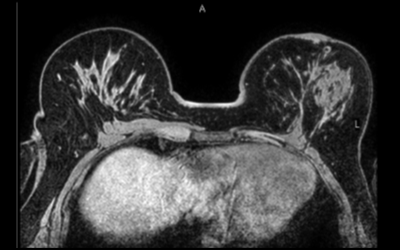

乳腺MRI : Breast MRI

造影剤を使った乳腺の検査です

乳腺MRIの検査は造影剤を使用し、うつ伏せで行う検査です。

乳がんの検出感度が高く、マンモグラフィのような圧迫による痛みはありません。遺伝的に乳がんに罹りやすい方に有効的な検査です。